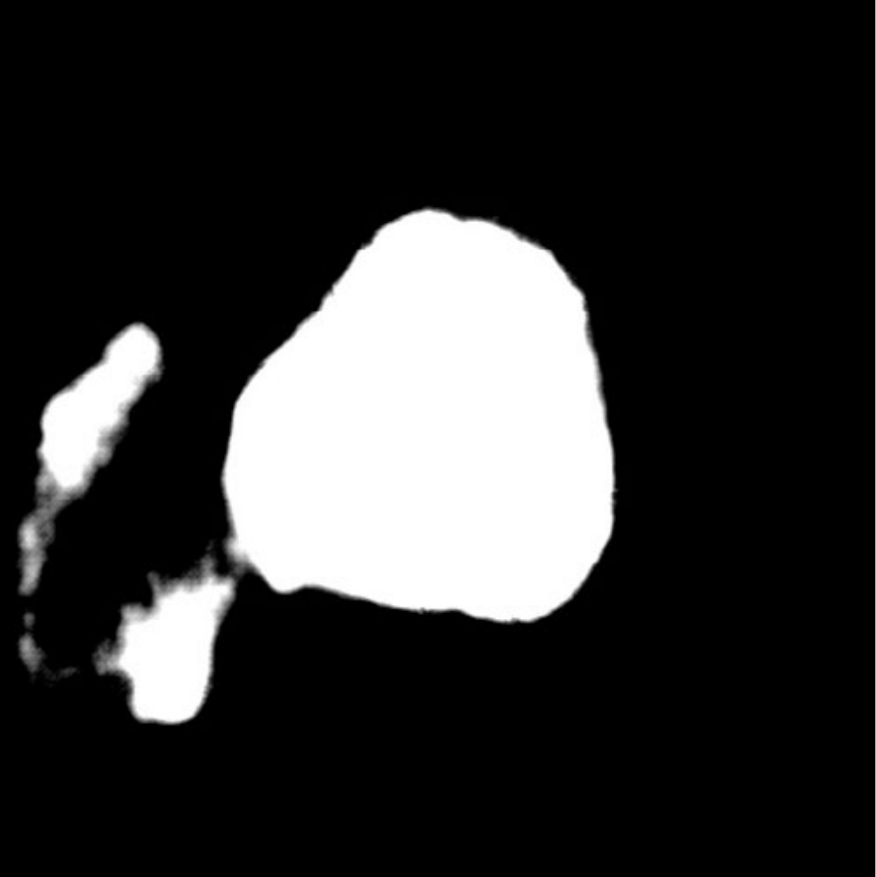

IV-C3 Results on BKAI-IGH NeoPolyp

![]() |

| (a) Inputs | (b) Ground Truth | (c) Ours | (d) EGE-UNet |

| (d) Swin-Unet | (e) MET-Net | (f) VM-UNetV2 | (g) UNet++ |

| Method | Binary | Multi-class | ||||

|---|---|---|---|---|---|---|

| MAE | Dice | IoU | MAE | Dice | IoU | |

| U-Net (2015) [1] | 0.99 | 87.25 | 81.33 | 0.92 | 67.74 | 64.11 |

| UNet++ (2020) [2] | 0.92 | 88.44 | 82.89 | 0.86 | 68.51 | 64.82 |

| EGE-UNet (2023) [28] | 3.20 | 59.98 | 49.28 | - | - | - |

| MISSFormer (2023) [8] | 0.95 | 87.98 | 81.89 | 0.87 | 70.00 | 66.40 |

| Swin-Unet (2023) [5] | 0.73 | 90.80 | 85.24 | 0.66 | 79.80 | 76.48 |

| MALUNet (2023) [29] | 1.84 | 82.09 | 69.67 | - | - | - |

| TransUNet (2024) [6] | 0.69 | 91.37 | 86.25 | 0.70 | 77.62 | 74.89 |

| MET-Net (2024) [30] | 0.74 | 91.05 | 85.99 | 0.71 | 75.96 | 73.07 |

| FSCA-Net (2024) [32] | 0.89 | 89.45 | 83.99 | 0.81 | 73.65 | 70.41 |

| VM-UNetV2 (2024) [33] | 1.26 | 87.71 | 78.16 | - | - | - |

| QTSeg (Ours) | 0.60 | 93.13 | 88.94 | 0.59 | 79.88 | 77.54 |

The experimental results of our QTSeg model on the BKAI-IGH Neopolyp dataset are presented in Table IV. The table clearly demonstrates that our QTSeg model achieves the highest scores across all metrics and tasks (binary and multi-class). Notably, QTSeg obtains the MAE, Acc, Dice, and IoU of 0.60, 99.40%, 93.13%, and 88.94%, and 0.59, 99.41%, 79.88%, and 77.54%, for the binary and multi-class tasks, respectively. Although EGE-UNet and MALUNet are characterized by their smaller parameter sizes, they struggle to converge on the poly-segmentation dataset due to inherent design limitations and model parameter constraints. In contrast, our QTSeg model demonstrates superior performance while maintaining competitive parameter values and lower FLOPs than the alternative methods. Regarding binary task, our QTSeg model achieves notable improvements of 1.76-33.15% in Dice and 2.69-39.66% in IoU. In terms of multi-class tasks, our QTSeg model gains notable improvements of 0.08-12.14% in Dice and 1.05-13.42% in IoU. The comparison in Fig. 7 showcases our model’s predictions alongside those of other methods. It is evident that our approach achieves more precise segmentation of the poly object with minimal error compared to the other methods.